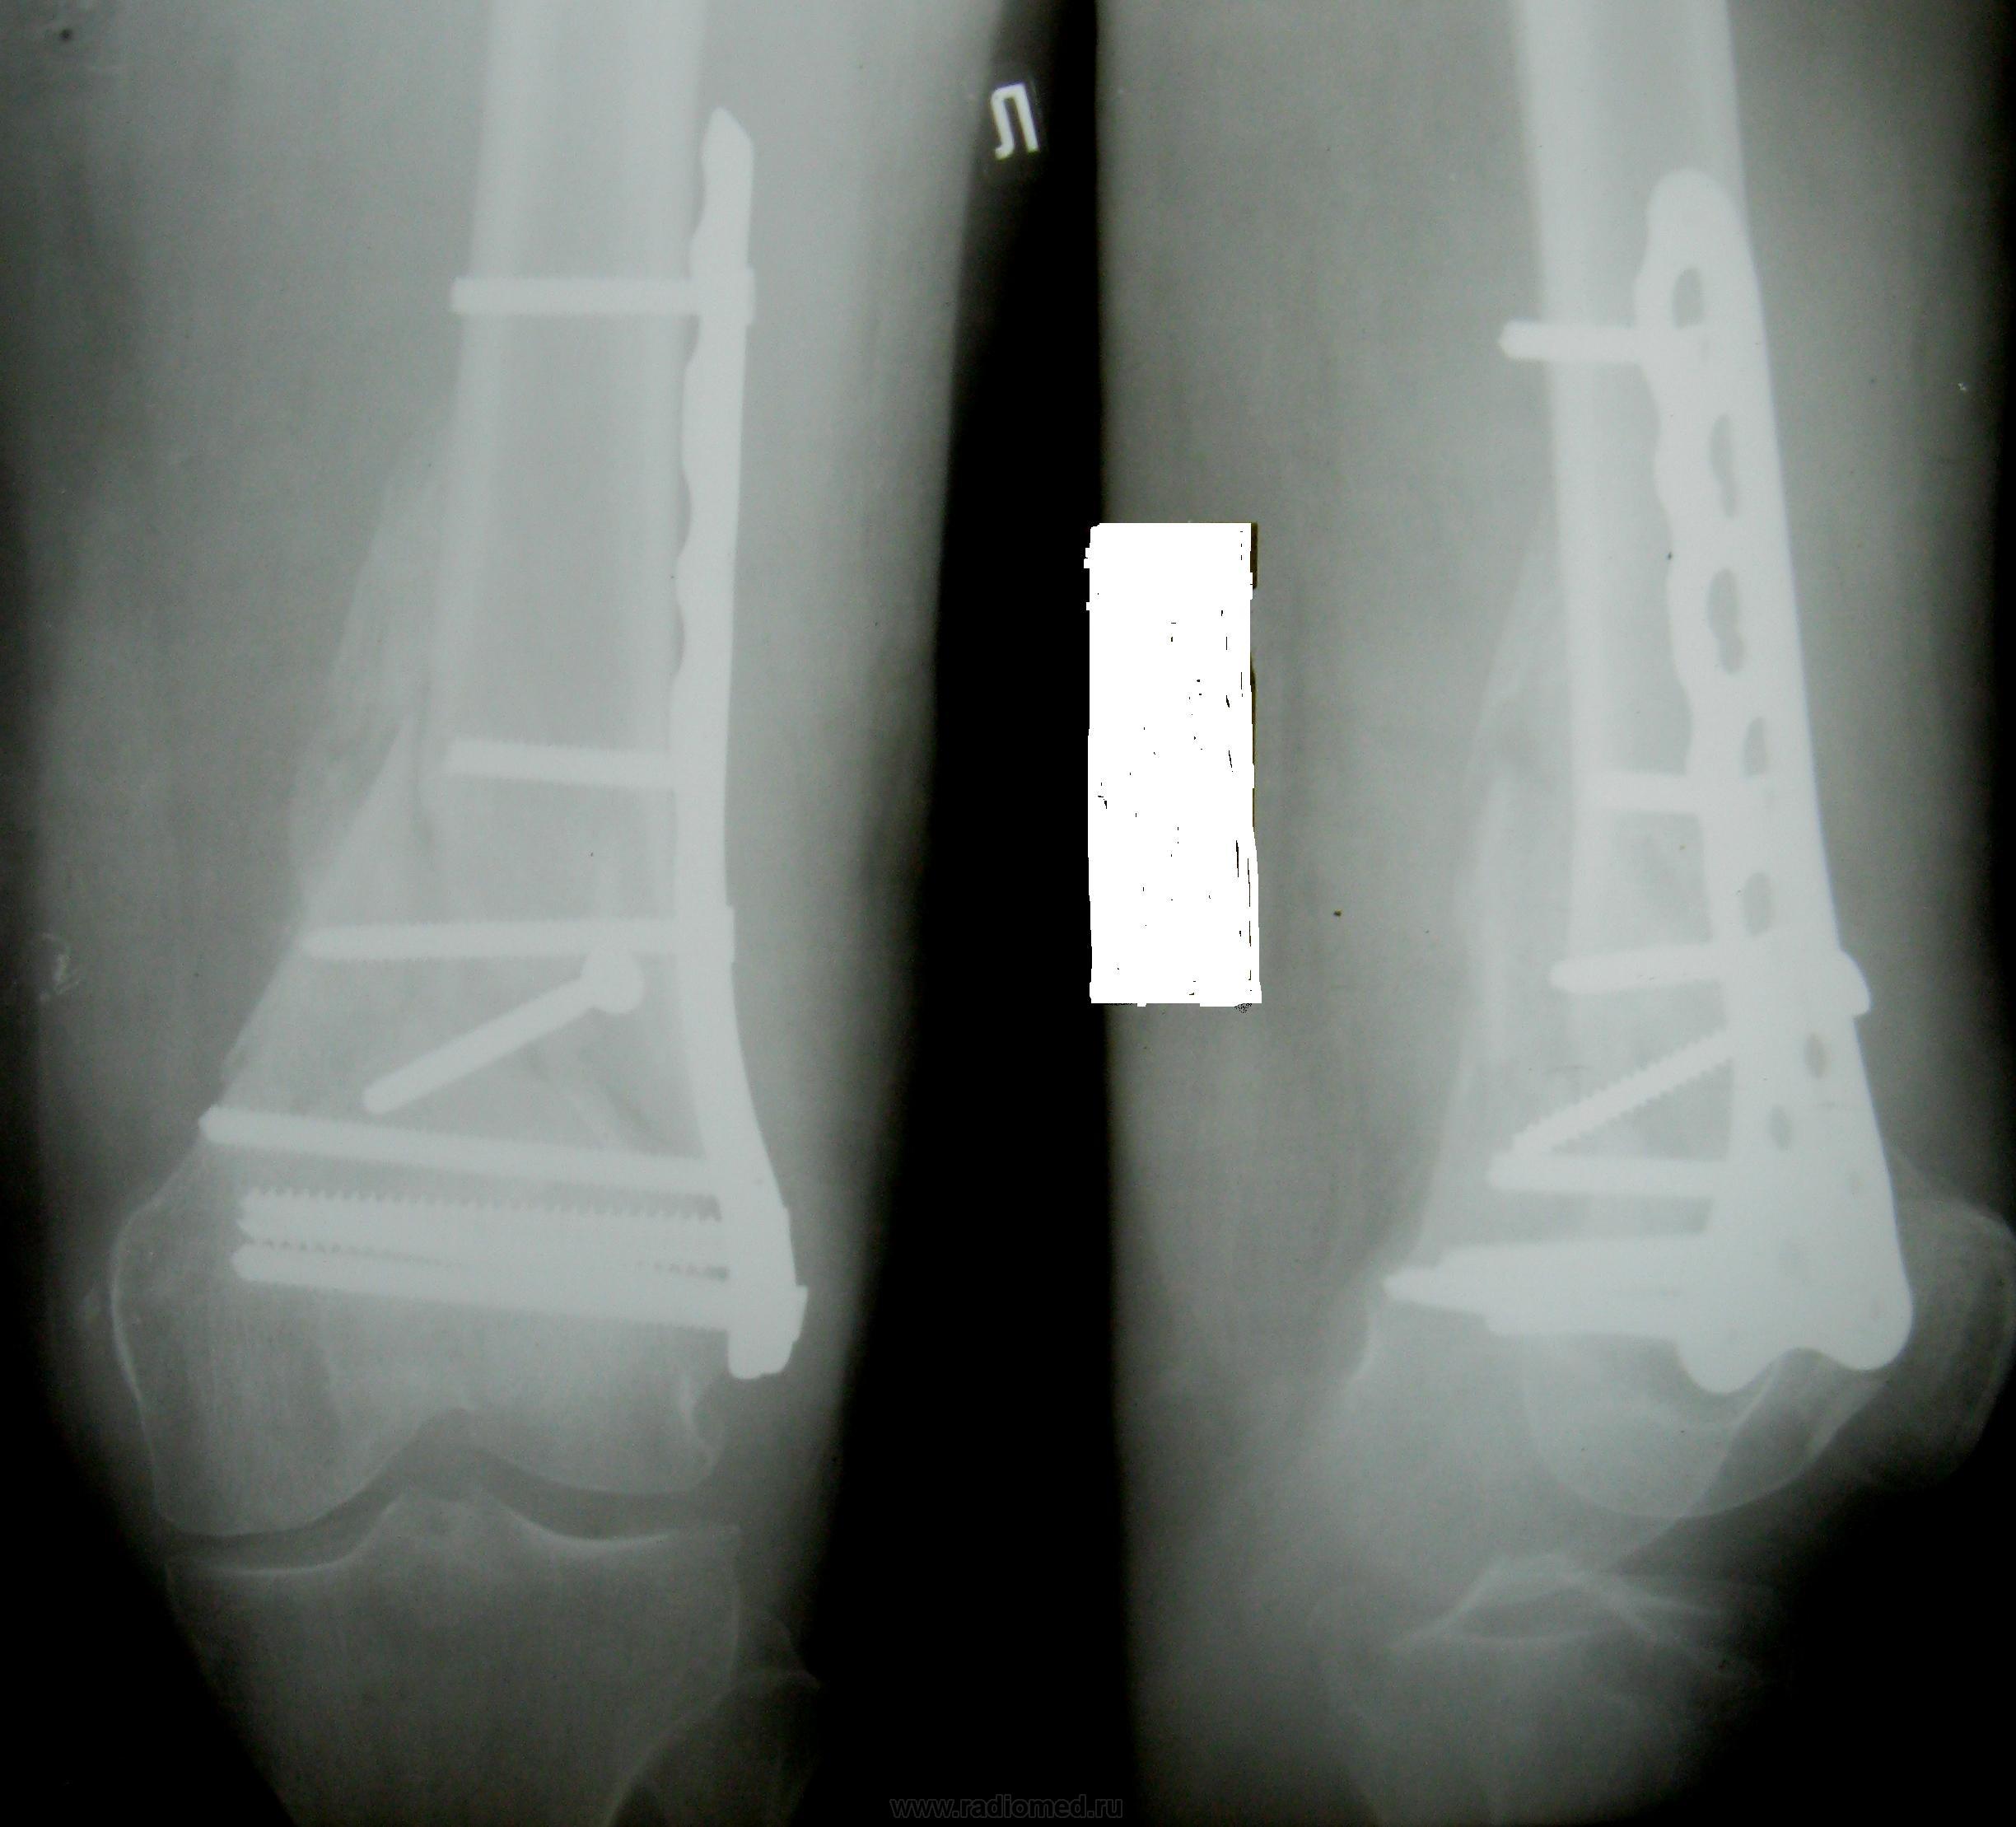

Хотелось бы узнать сроки последней рентгенографии после МОС. Мозоль формируется достаточной, закономерно избыточной при условии данного пространственного расположения отломков. Однако, видимо имеется минимальная подвижность, потому что как раз там, где костный мостик должен "схватиться" он прерывается. Похоже, предется продлить иммобилизацию. Тем более, что репозиция не идеальная, ось бедра биомеханически дислоцирована латерально и вся нагрузка ляжет на наружные мыщелки, что приведет со временем к прогрессированию гонартроза, который и так в наличии.

1.Срок между первой и четвертой (она сдублирована) рентгенограммами около 3-х месяцев.

2.Это самый главный момент, который меня тревожит, создается впечатление об уже ФОРМИРУЮЩЕМСЯ псевдоартрозе.

3. Вне всякого сомнения - гонартроз есть и он, к сожалению, будет прогрессировать.

Вывод - нужны решительные действия по поводу формирующегося псевдоартроза. Какие - это уже не нам решать....